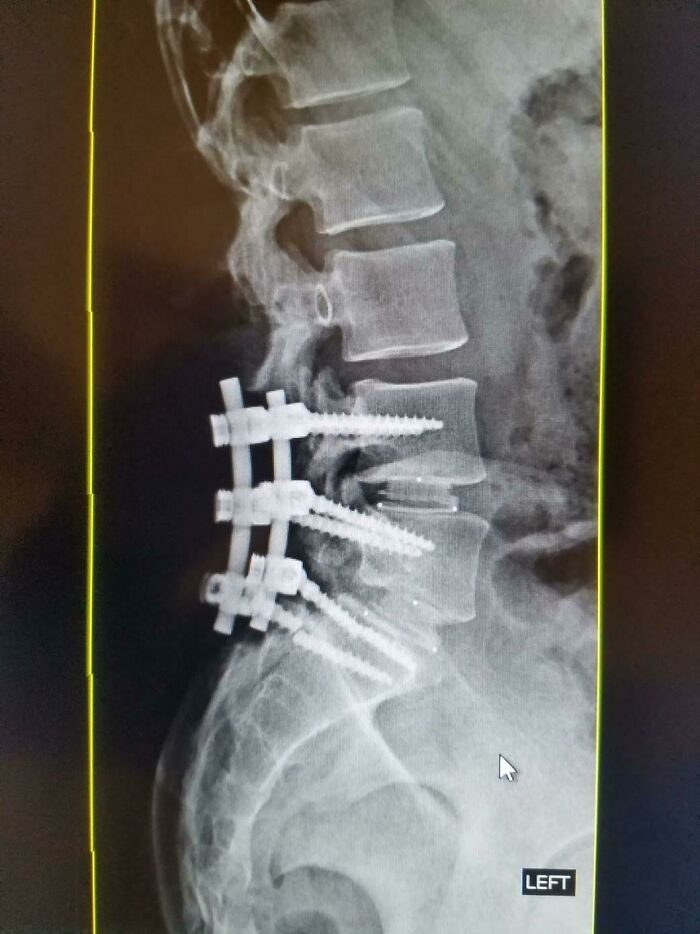

33. „Тот самый случай, когда я сломал один из винтов в спине“